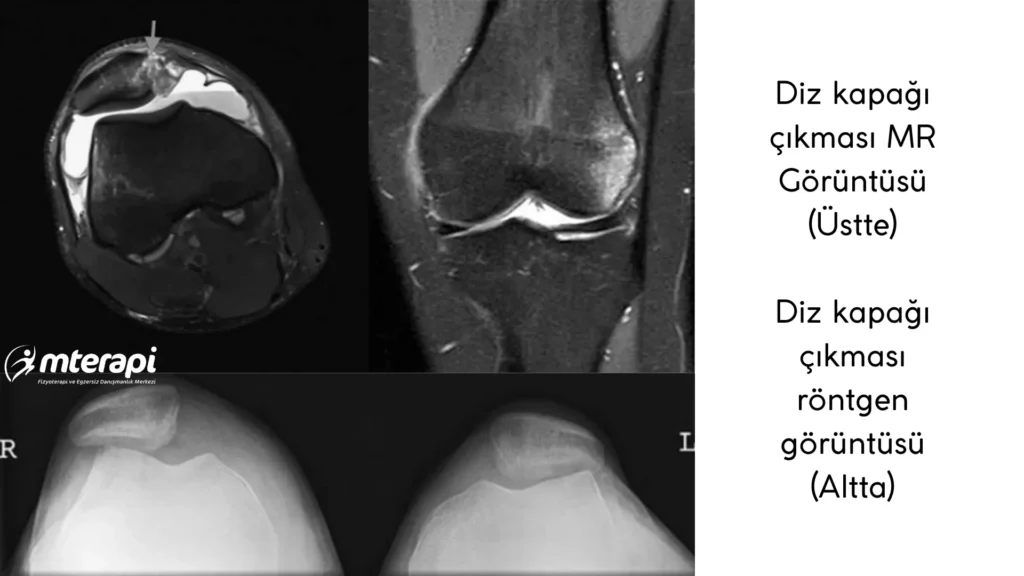

Diz Kapağı Çıkmasında Görüntüleme (Röntgen ve MR Neden Gerekir?)

Diz kapağı çıkmasında doğru tanı koymak ve en uygun tedaviyi seçmek için görüntüleme yöntemleri büyük önem taşır. Çünkü bazı bulgular yalnızca muayene ile fark edilemez ve özellikle kemik veya kıkırdak hasarı varsa tedavi planı tamamen değişebilir.

Her diz kapağı çıkmasında mutlaka ilk yapılması gereken görüntüleme röntgendir.

Röntgen, diz kapağının yerinden ne kadar çıktığını, normalde oturduğu oluktan kayıp kaymadığını ve herhangi bir kemik parçasının kırılıp kırılmadığını gösterir. Bu nedenle standart ön-arka, yan ve özellikle “axial – Merchant” adı verilen özel bir açıyla çekilmiş görüntüler istenir. Bu özel açı, diz kapağının her iki dizle karşılaştırılarak dışa doğru kayıp kaymadığını net bir şekilde gösterir.

Röntgende bazen diz kapağının iç tarafında küçük kırık parçaları, eklem yüzeyinde bozulma veya kopmuş kıkırdak parçaları görülebilir. Bu bulgular, ameliyat gerekip gerekmediğini belirlemede oldukça önemlidir.

Röntgenden sonra çoğu hastada MR çekilmesi önerilir.

MR, özellikle kıkırdak ve bağ dokularını çok daha net gösterdiği için diz kapağını yerinde tutan MPFL bağının (iç yan bağlardan biri) nereden ve nasıl yırtıldığını değerlendirmeyi sağlar. MPFL yırtıkları genellikle üç farklı bölgede oluşabilir: bağın patellaya tutunduğu yer, bağın orta kısmı veya bağın uyluk kemiğine tutunduğu bölge. Bu ayrım önemlidir, çünkü yırtığın yeri ve şekli tedavi planını doğrudan etkileyebilir.

Ayrıca MR ile dizdeki gizli kıkırdak kırıkları, eklem içi serbest dolaşan parçalar ve diz kapağının çıkmasına neden olabilecek yapısal anormallikler (trochlear displazi, patella alta gibi) ayrıntılı şekilde görülebilir.

Diz kapağı çıkmalarında kemik ve kıkırdak hasarının oranı yüksek olduğundan MR’ın çok geciktirilmeden, mümkünse yaralanmadan kısa süre sonra yapılması önerilir. Bu sayede hem tanı kesinleşir hem de tedavi süreci daha doğru şekilde planlanır.